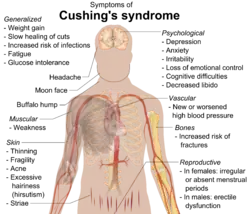

Multiple mental and physical illnesses, along with some of the medications that treat such illnesses can increase someone's risk of obesity.[16] Some examples of other illnesses are hypothyroidism, Cushing's syndrome, and growth hormone deficiency.